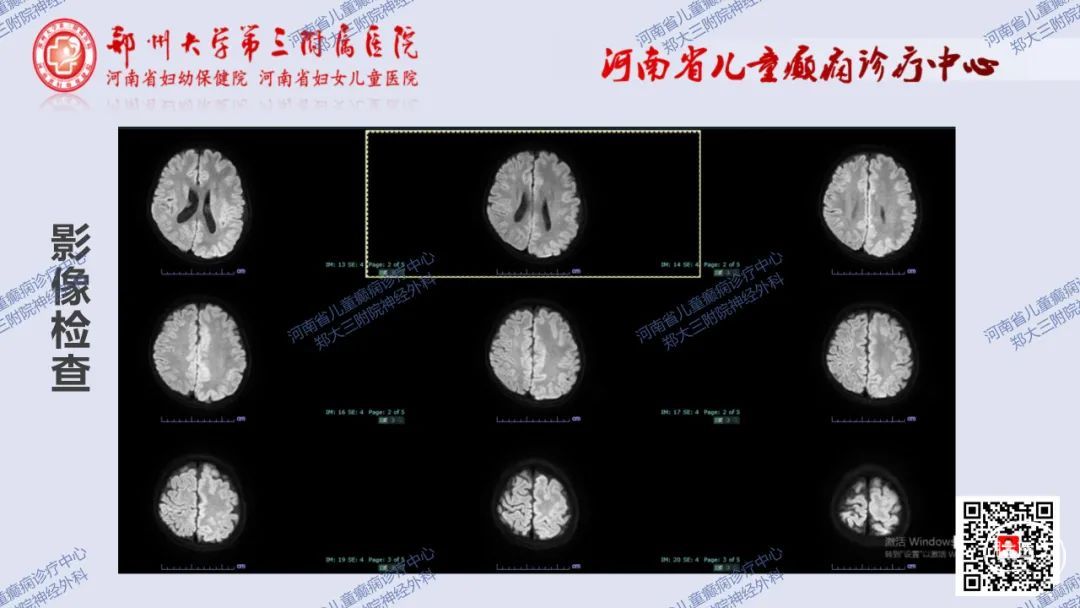

术战癫峰第57期左侧巨脑回畸形行大脑半球离断术一例

图片尺寸1080x608